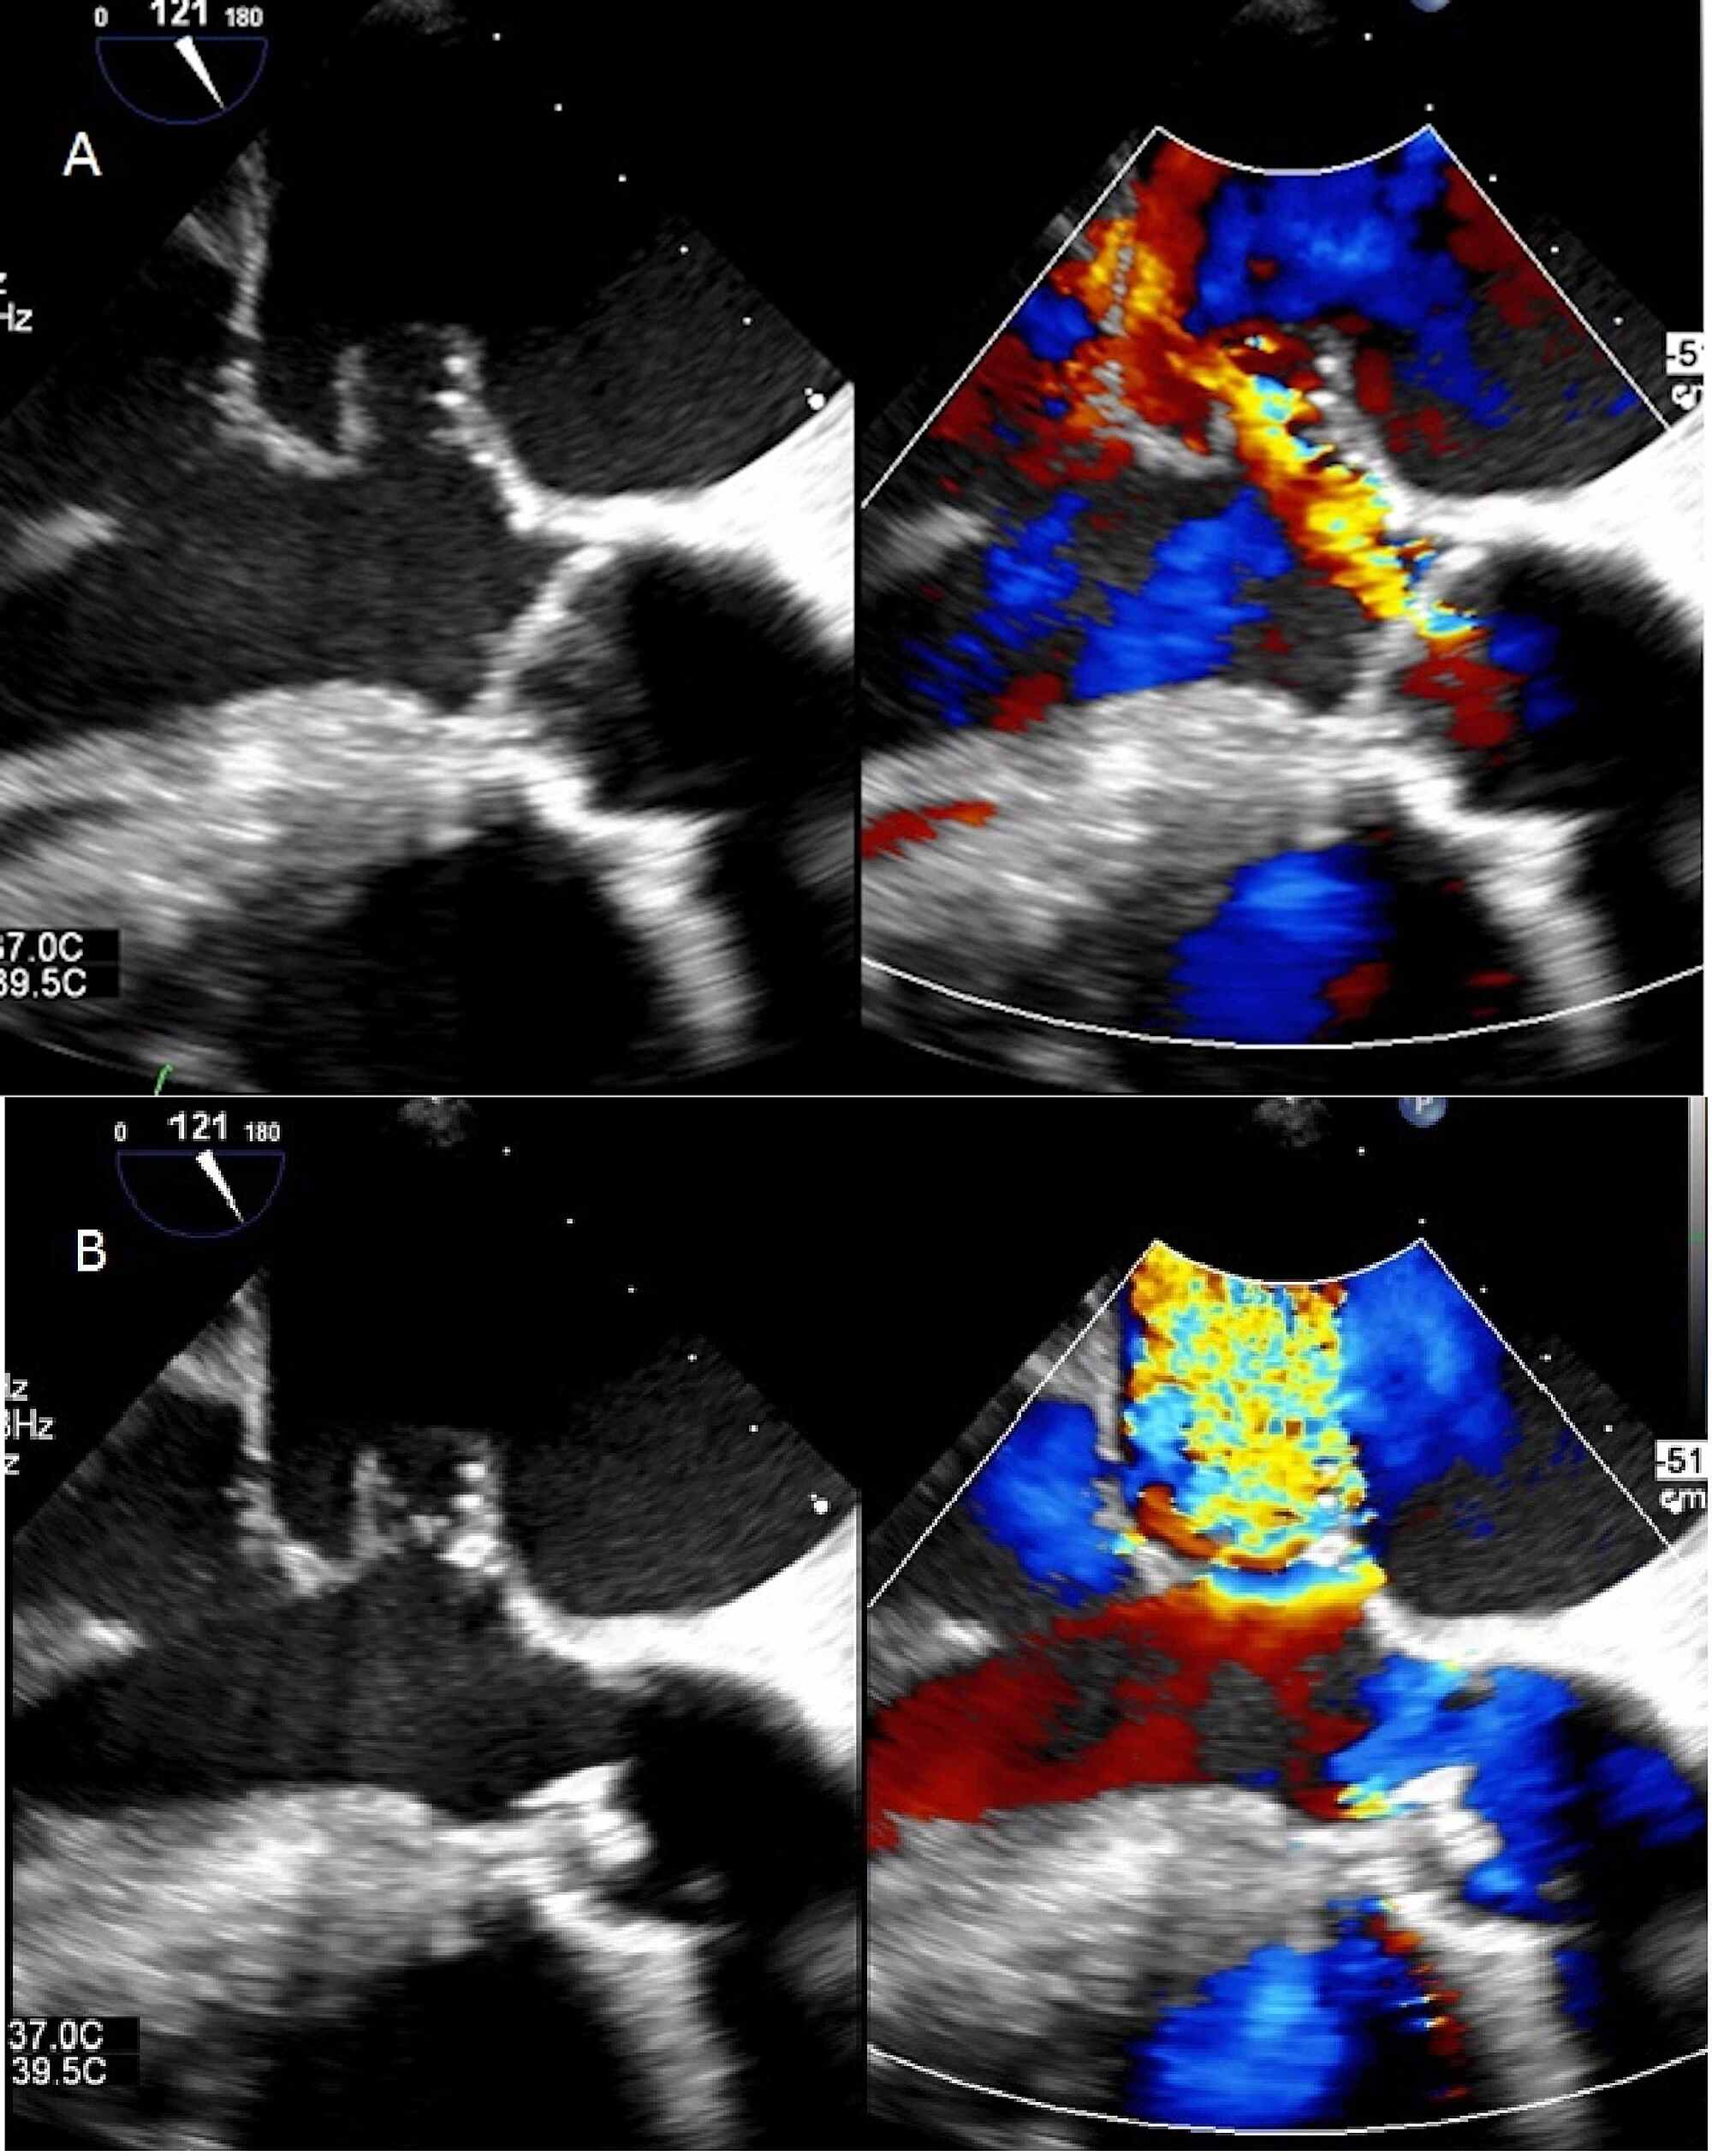

From www.researchgate.net

Transesophageal echocardiogram revealing vegetation on the mitral valve What Happens When A Heart Valve Rupture papillary muscle rupture is one of the catastrophic mechanical complications following myocardial. to understand the causes of heart valve disease, it may be helpful to know how the heart works. myocardial rupture occurs in the setting of acute myocardial infarction (ami), blunt and penetrating cardiac. aortic valve damage (aortic regurgitation) or rupture into the lining around. What Happens When A Heart Valve Rupture.

Mitral Valve Perforation Closure Result on Transesophageal What Happens When A Heart Valve Rupture myocardial rupture occurs in the setting of acute myocardial infarction (ami), blunt and penetrating cardiac. In this condition, the valve between the left heart. mitral valve regurgitation is the most common type of heart valve disease. to understand the causes of heart valve disease, it may be helpful to know how the heart works. aortic valve. What Happens When A Heart Valve Rupture.